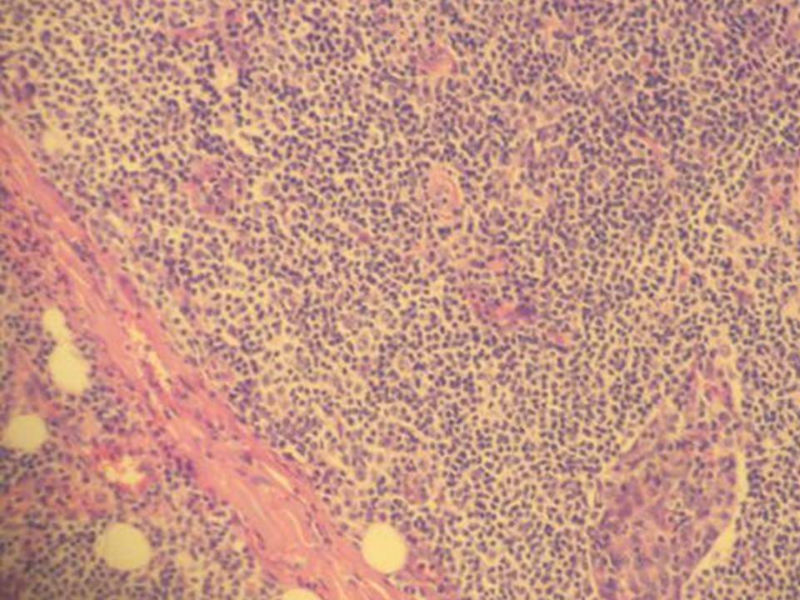

女,71岁,腮腺肿物,临床诊断混合瘤。

图1